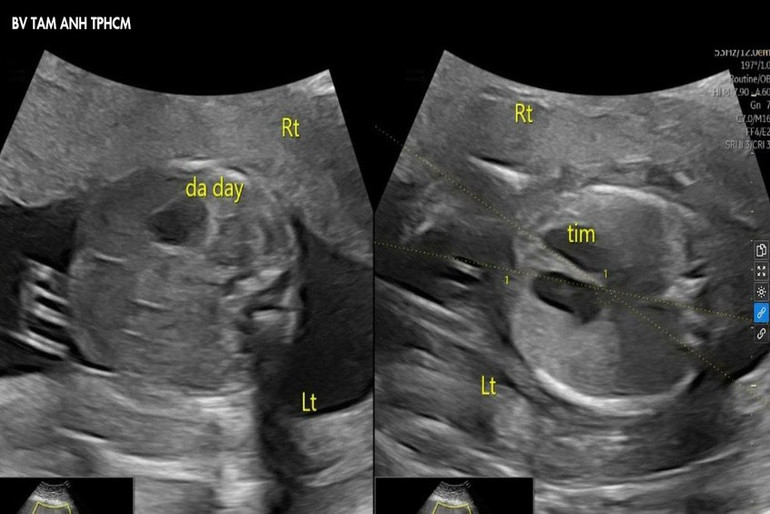

Thạc sĩ, bác sĩ Nguyễn Thị Liên Phương, chuyên khoa Y học bào thai, siêu âm phát hiện tim và dạ dày thai nhi nằm ở bên phải (bình thường ở bên trái), biểu hiện của đảo ngược phủ tạng. Đây là tình trạng các cơ quan trong cơ thể nằm ngược lại so với vị trí giải phẫu bình thường.

Hình ảnh siêu âm cho thấy tim và dạ dày của thai nhi nằm ở bên phải.

Ở trường hợp này, siêu âm thai định kỳ xác nhận các cơ quan của thai nhi bị đảo ngược theo kiểu “soi gương”, không có dị tật đi kèm. Điều này rất hiếm gặp, y văn thế giới chưa có thống kê đầy đủ. Trẻ có tiên lượng tích cực, khả năng không gây ra vấn đề sức khỏe nghiêm trọng cho trẻ.